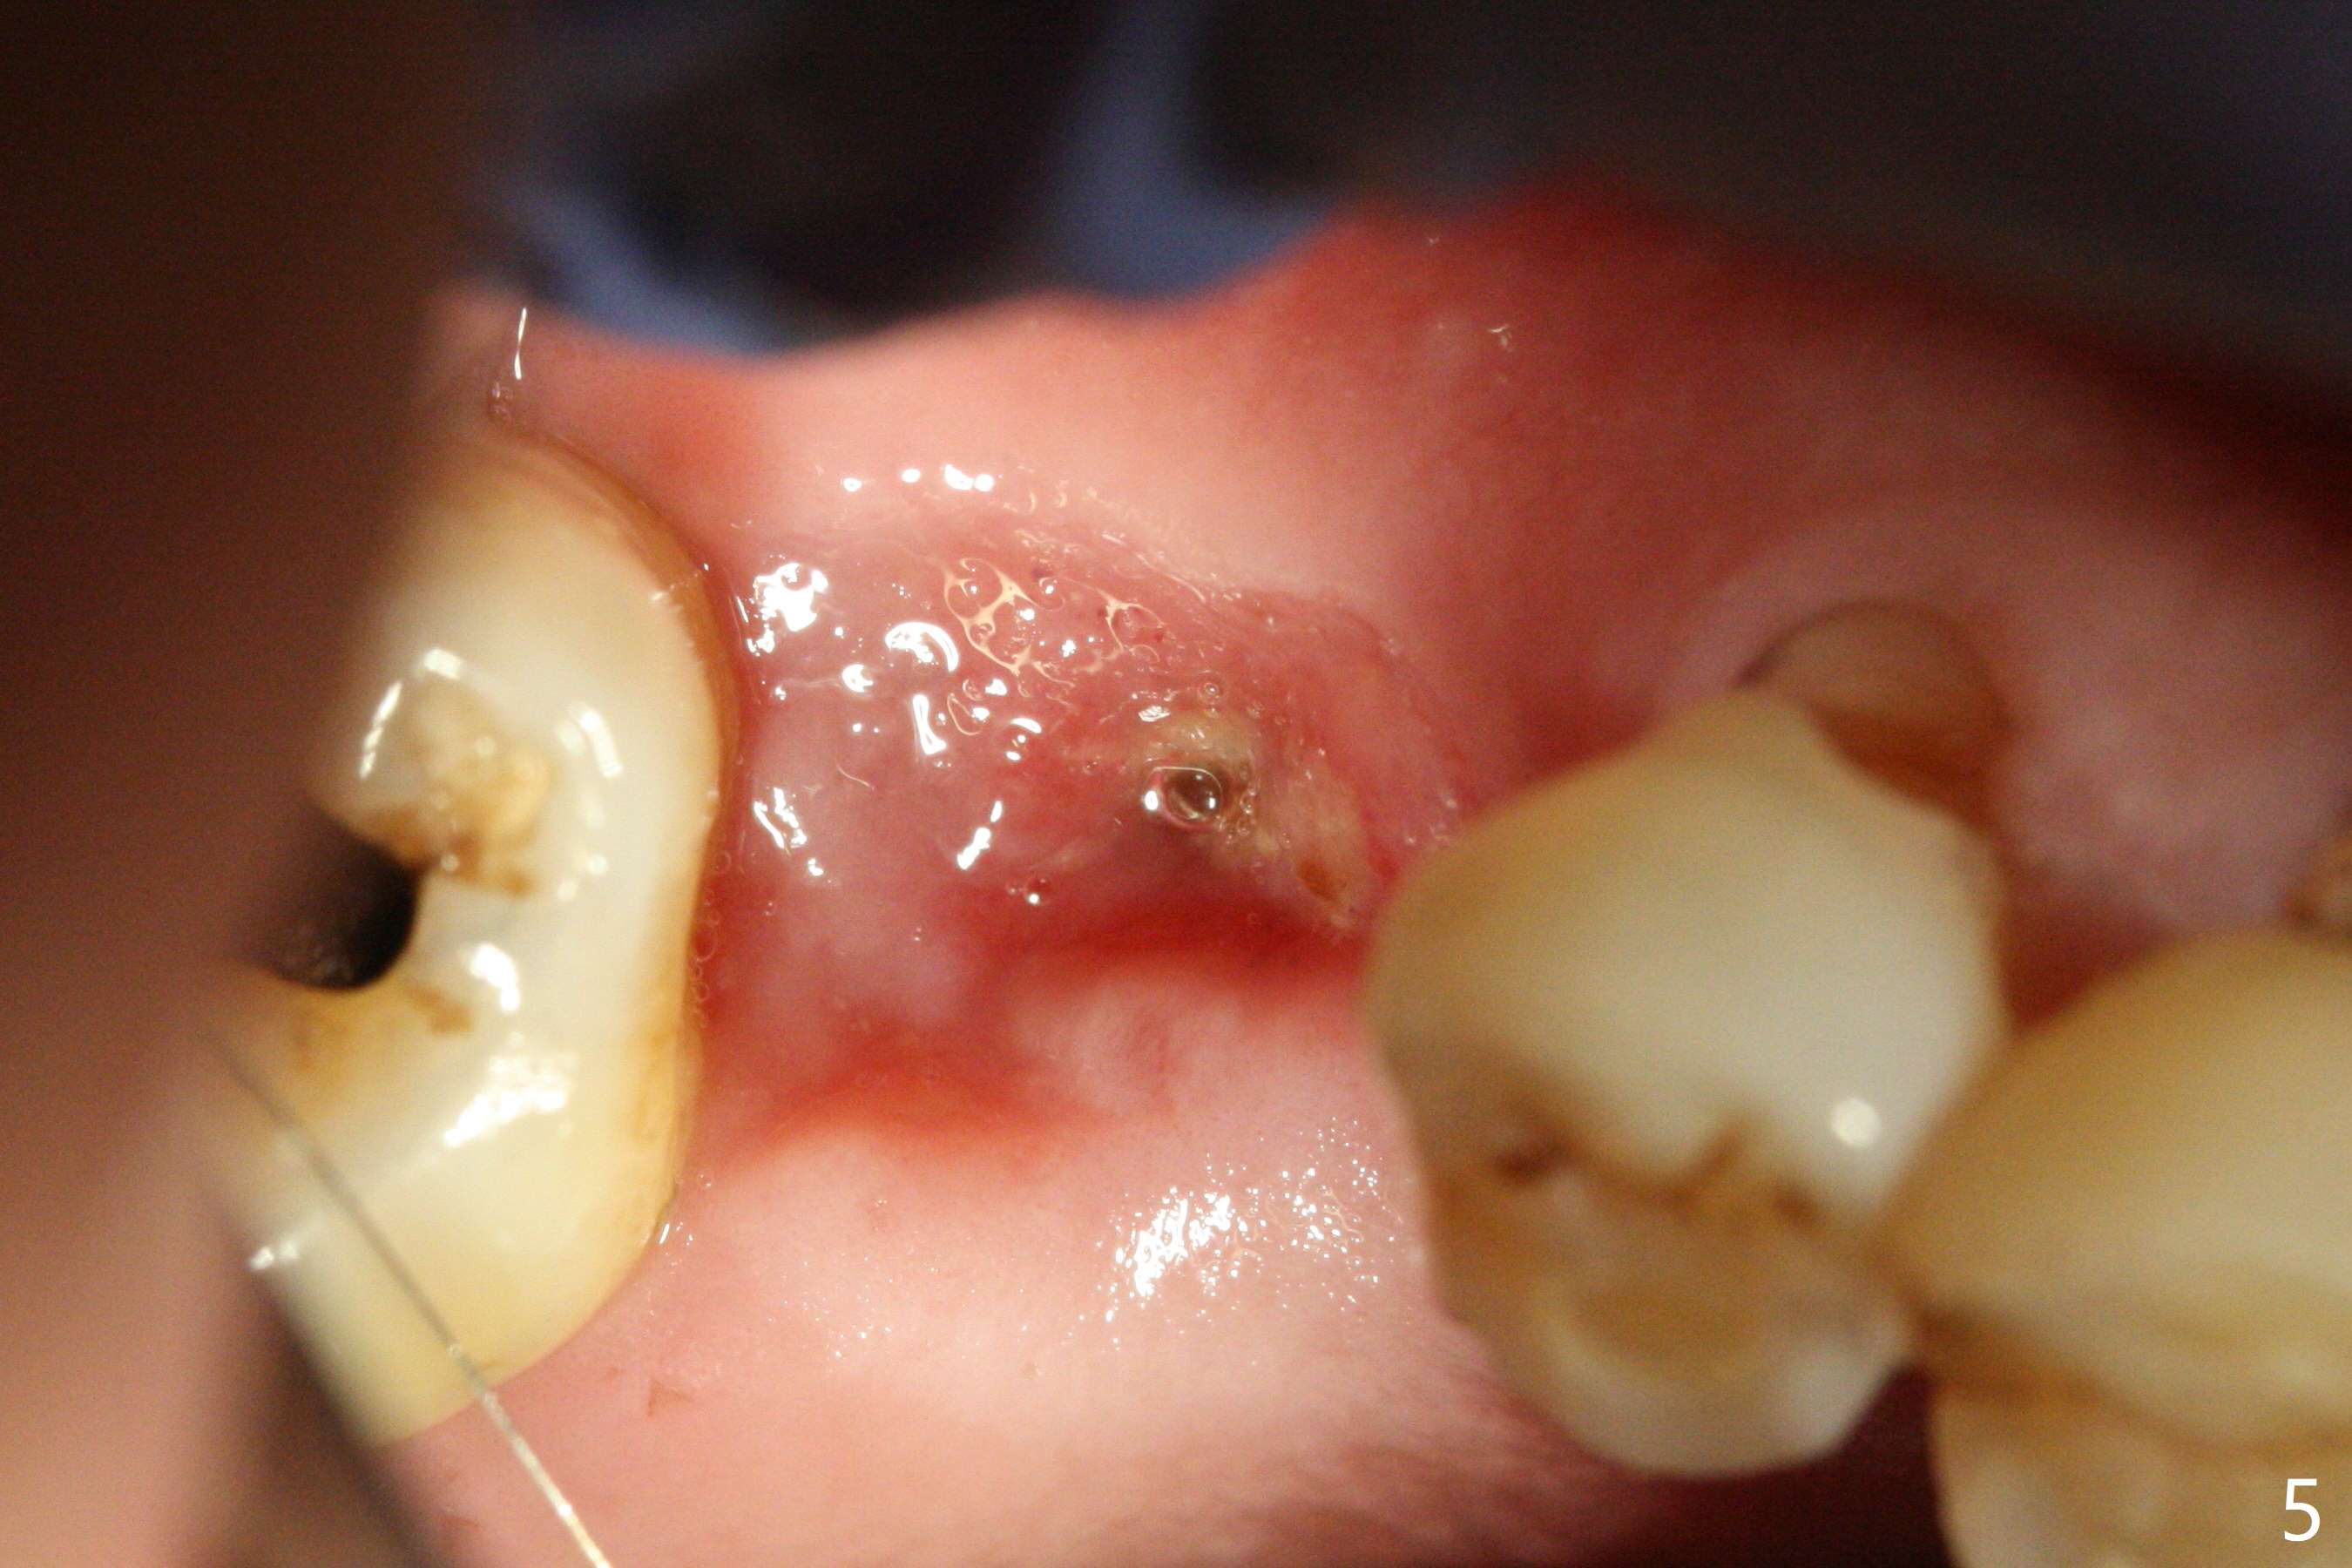

The clearance between the residual roots of the tooth #3 and the abutment at #30 seems to be somewhat limited (Fig.1). The initial osteotomy depth is 10 mm (Fig.2). After moving the osteotomy mesially, the depth increases to 12 mm; a parallel pin is inserted for 16 mm (Fig.3 with sinus membrane perforation). The depth of the rest of the osteotomy is 10 mm with placement of a 5x10 mm implant with >50 Ncm (Fig.4); with insertion of a 6.8x4(3) mm abutment and Vera Graft (*), an immediate provisional is fabricated. Collagen plug is used to seal the gap between the provisional and the gingiva. The abutment dislodges nearly 1 month postop; the wound has healed (Fig.5). A 8.2x5(4) mm healing abutment is placed to keep the soft tissue configurement.